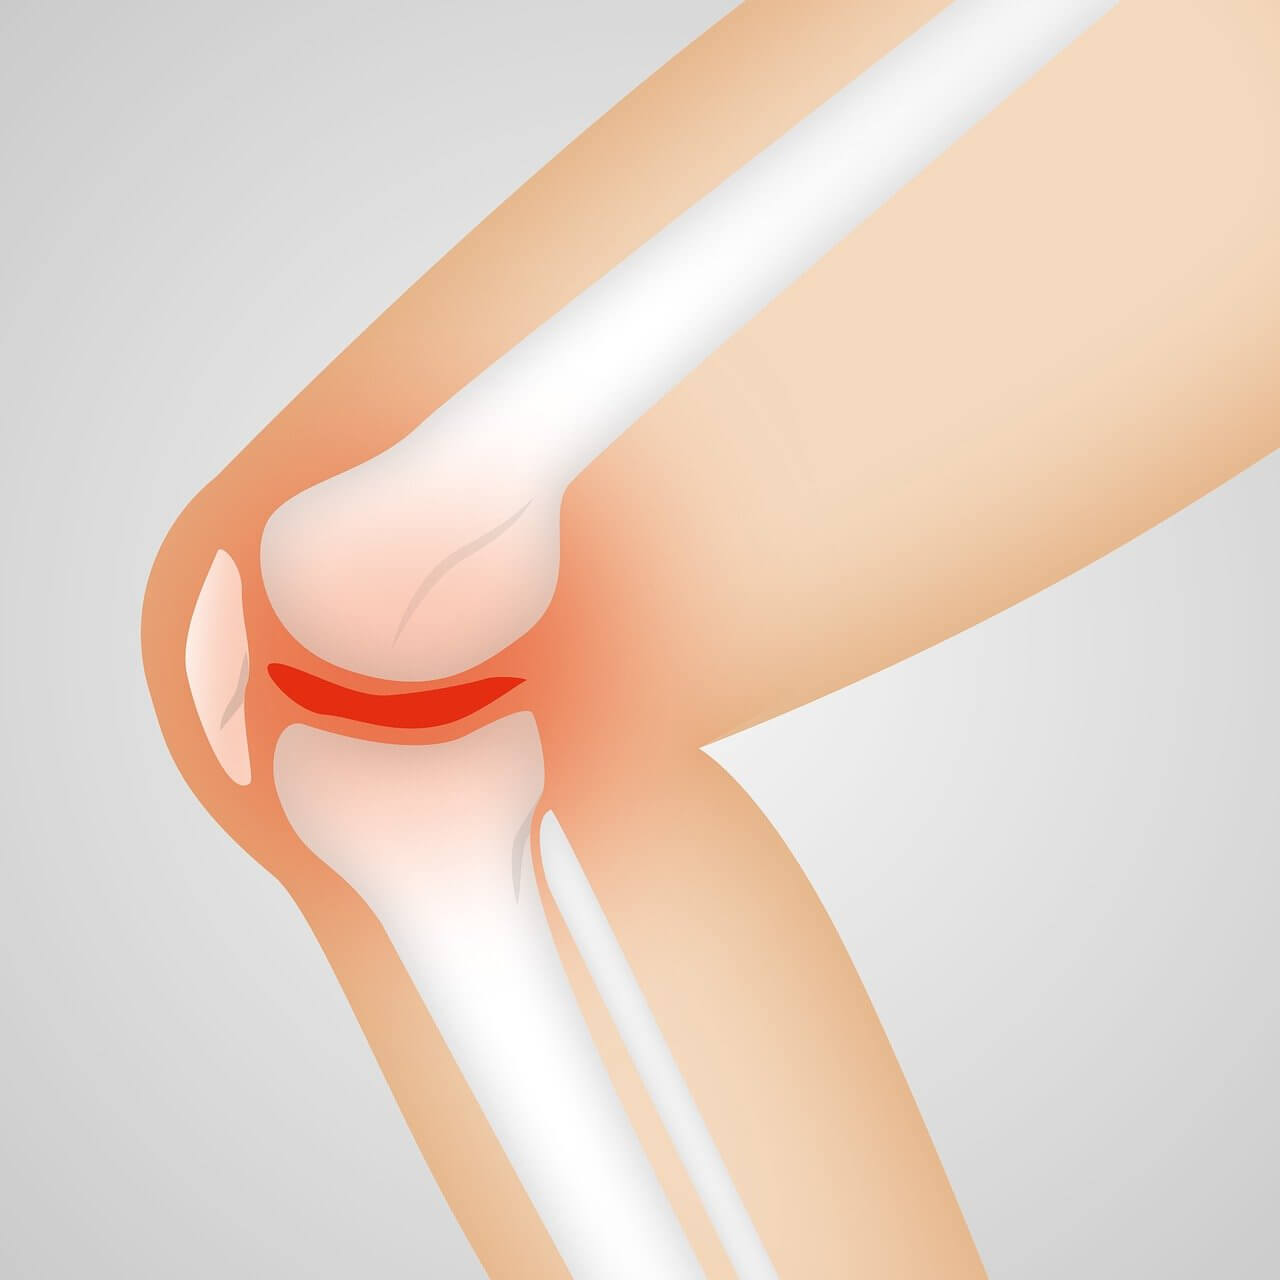

- 연골 손상

연골은 뼈와 뼈 사이를 보호하는 완충재 역할을 합니다. 그러나 반복적 충격, 과체중, 노화로 연골이 손상되면 무릎 통증의 원인이 됩니다.

- 퇴행성 관절염

50대 이후 가장 흔한 무릎 통증의 원인은 퇴행성 관절염입니다. 연골이 닳아 없어지며 뼈끼리 맞닿아 통증과 변형이 발생합니다.